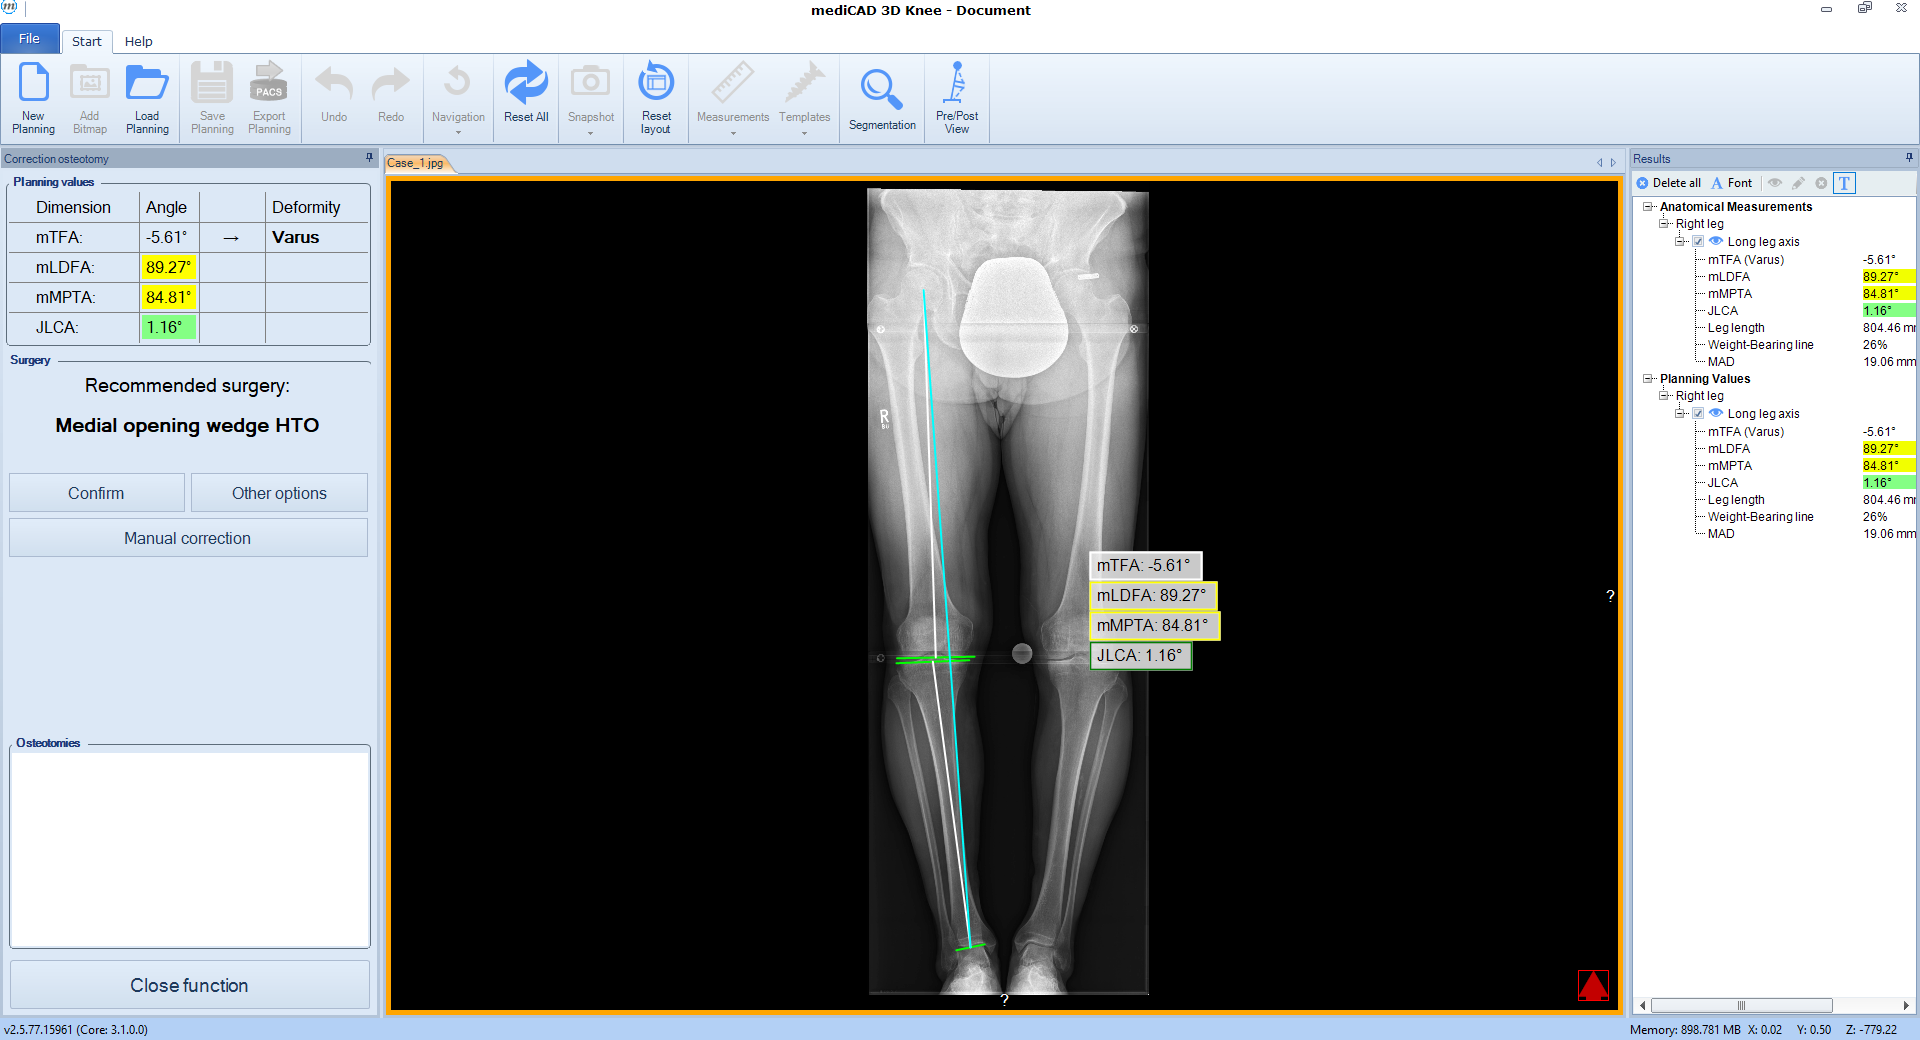

The software automatically detects all necessary landmarks (Fig 1). Based on their position (which can be adjusted manually) the software calculates all essential values (axis, joint lines, and angles) and delivers a detailed report. A traffic light system illustrates normal, intermediate, or pathological values.

Following the deformity analysis, the software automatically recommends a surgical procedure, eg, medial opening wedge high tibia osteotomy, depending on the type of deformity (Fig 2). The user can follow the proposed procedure or choose individual options.

Case 1

(Case provided by Stefan Schröter)

A 33-year-old woman complained of pain in the lateral compartment after a normal working day. Sports activities were no longer possible. Free range of motion (ROM: 0/0/150°), ligaments in sagittal, and coronal planes were stable. There was no effusion. The patient had valgus deformity which was corrected with a distal femoral osteotomy.